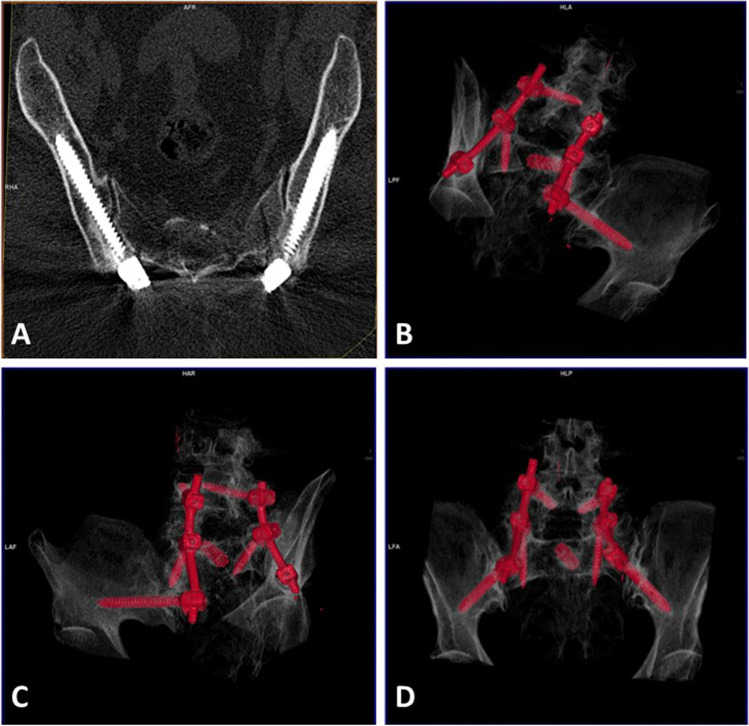

Fig. 4.

A An AI case, where iliac screws correlate with the ideal trajectory. On 3D reconstruction (B–D), on the inlet view of the pelvis, the screws are centered in the iliac view

Our analysis illustrated that AI correlates better with the ideal trajectory (Fig. 4). In fact, the trajectory never crosses the sacroiliac joint and the entry point is similar to the one achieved by the longest and thickest screw possible that could fit into the channel. The narrowest point of the iliac channel is just above the sciatic notch, where the anchoring for iliac screws is critical to avoid violations toward the sciatic notch [22]. The feasibility of S2AI screw insertion, into the sacrum and ilium, has been identified and previously described for clinical practice [9]. With screws similar to those used in our series, increased feasibility could be achieved given that it would be easier to get its modification once the SI joint is crossed.